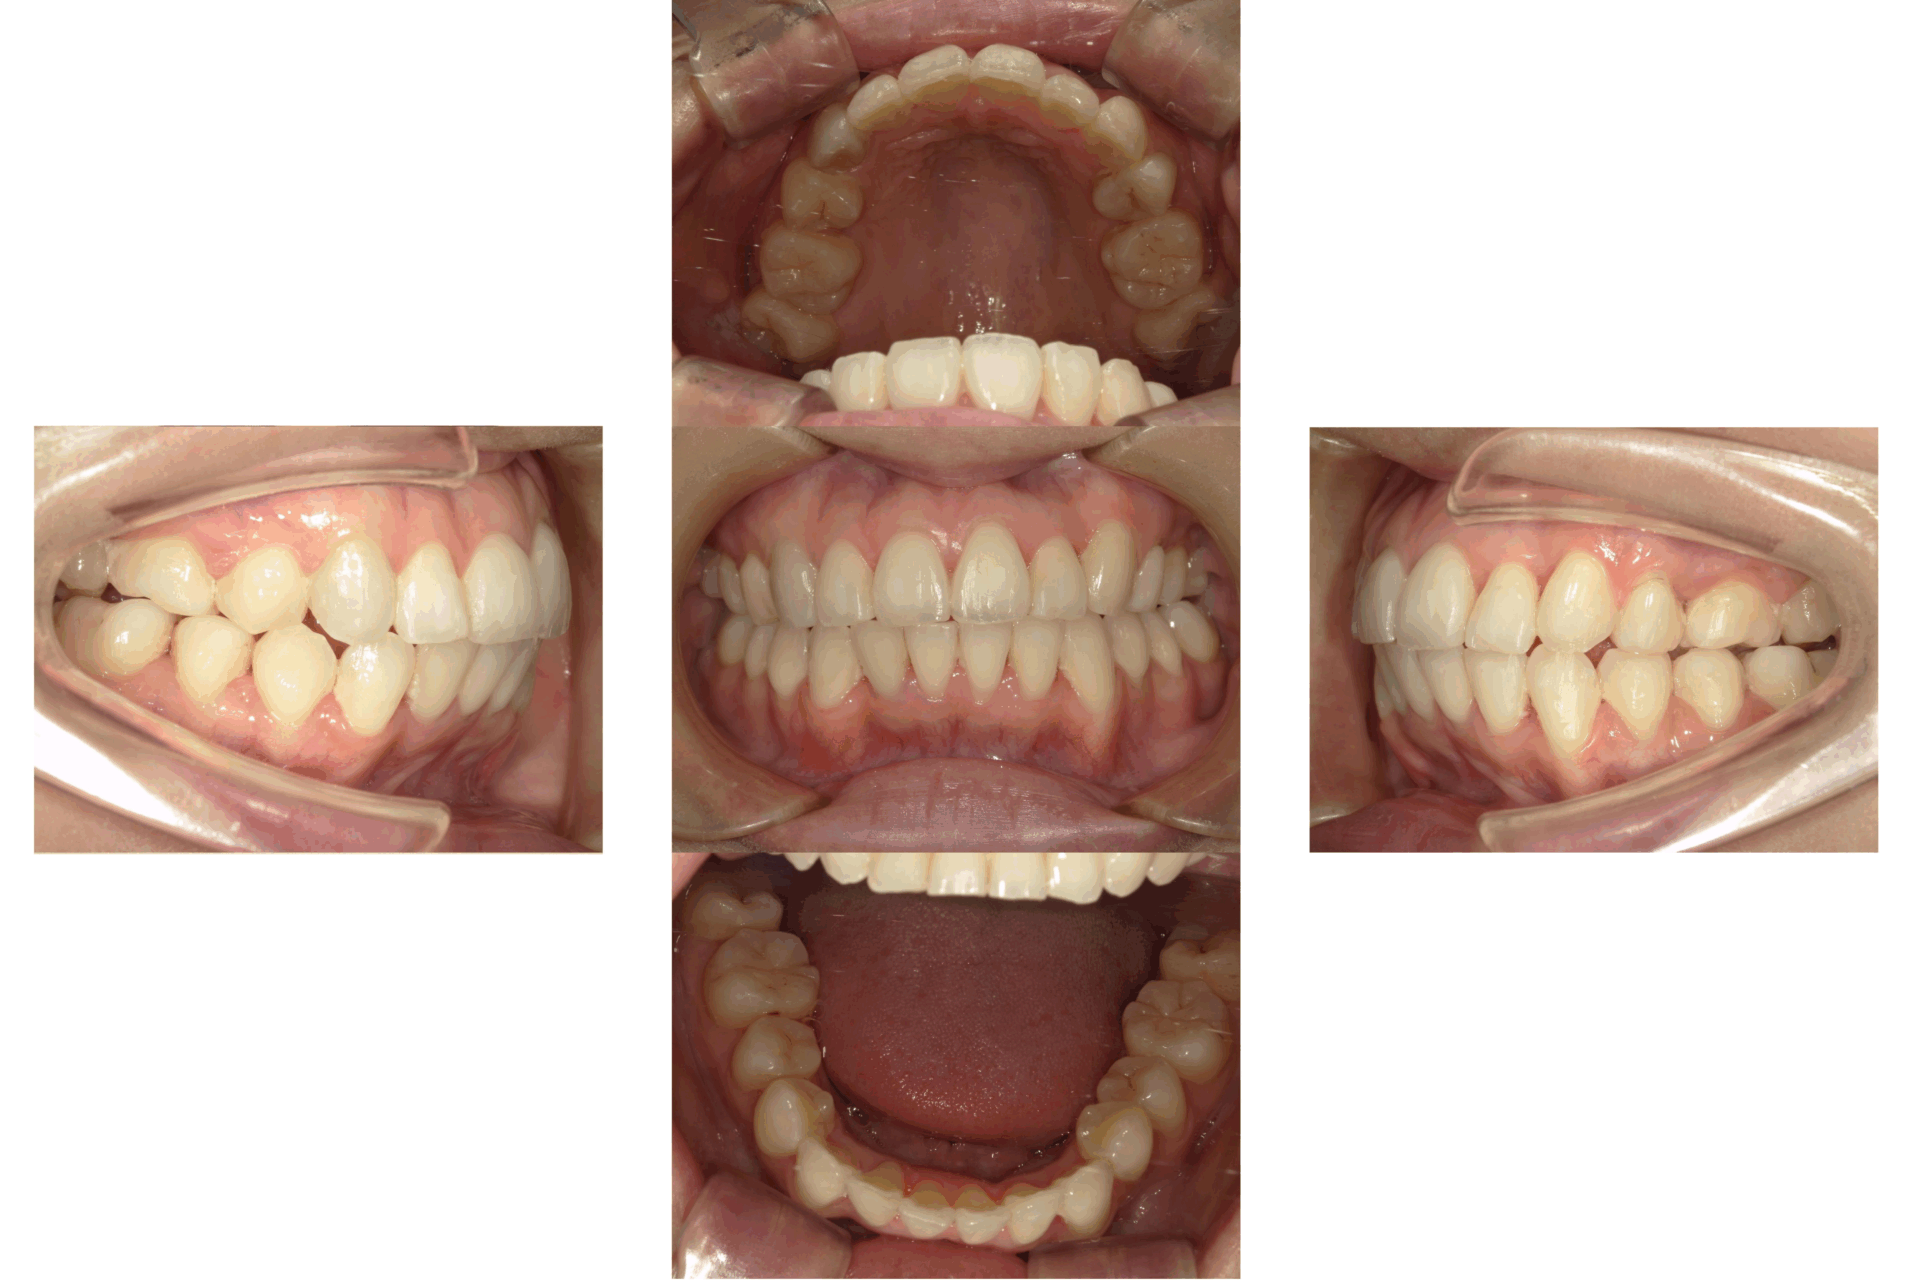

20代、男性、ワイヤー

| 施術内容 | 主訴:上前歯が出ている。下がデコボコ。なるべく歯を抜きたくない。 詳細:マウスピース矯正を装着しての歯並び改善 |

| 治療期間 | 12ヶ月(12/16現在 治療終了) |

| リスク・副作用 | ■リスク・副作用 ・治療の初期段階では、痛みや不快感が生じやすくなりますが、一週間前後で慣れます。 ・歯の動き方には個人差があるため、予想された治療期間より延長する場合があります。 |

| 費用 | 枚数無制限 48万(税込528,000円) |